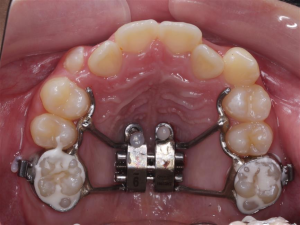

Hàm nong nhanh MSE (Maxillary Skeletal Expansion)

Trong trường hợp bệnh nhân đã bước vào giai đoạn sau của thời kỳ tăng trưởng, đường khớp giữa hàm trên bắt đầu gắn chặt hơn, các minivis có thể được cắm vào xương để hỗ trợ việc nong rộng hàm (phương pháp MARPE – Miniscrew assisted rapid palatal expander).

Phức tạp hơn, nếu bệnh nhân đã bước vào tuổi trưởng thành, đường khớp đóng hoàn toàn, mức độ bất hài hòa kích thước hàm trên lớn, phương án phối hợp phẫu thuật để mở rộng cung hàm có thể được chỉ định (SARPE – Surgical assisted rapid palatal expander).

Hàm nong nhanh có hỗ trợ của minivis (MARPE)